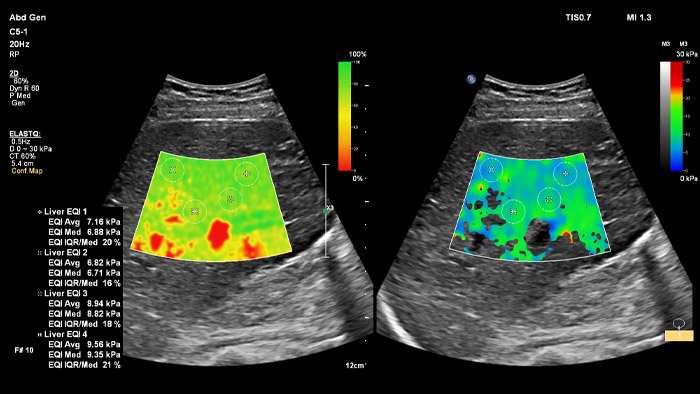

ElastQ fournit une évaluation en temps réel de la rigidité des tissus par ondes de cisaillement 2D (2D-SWE) qui est non invasive, reproductible et facile à réaliser. ElastQ offre également la possibilité d'effectuer des mesures rétrospectives sur des images stockées et comprend une carte de confiance pour un affichage précis de la propagation des ondes de cisaillement.

Imagerie avec ElastQ